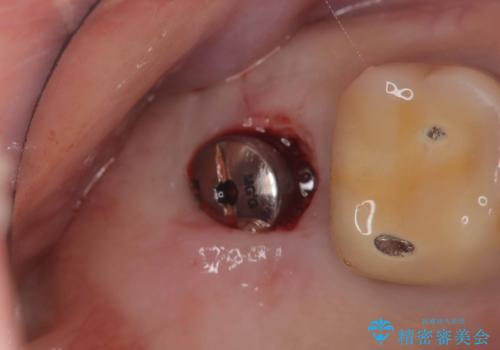

抜歯と歯根嚢胞の除去を行った後、インプラントで治療しました。治療後は「自分の歯のように咬める」と大変ご満足いただけました。